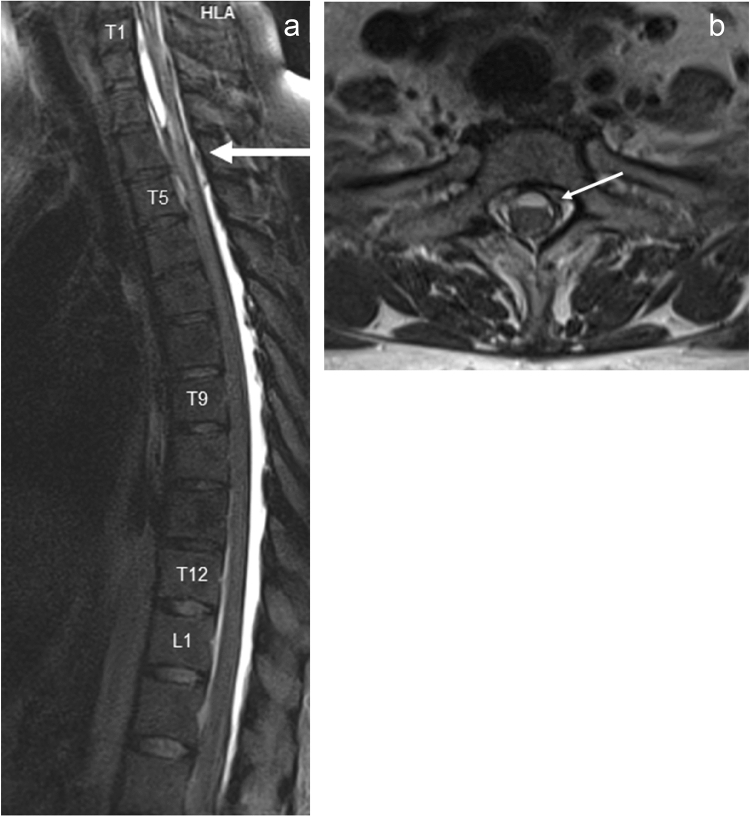

K.M., male, aged 26, with known insulin-dependent diabetes and hypothyroidism, transferred to the Neurosurgery Ward on 5 February 2016 from Medical Ward of another hospital, where he had been treated for abnormal glycemic levels and persistent vomitus. Further diagnostic procedures revealed obstructive hydrocephalus in the course of posterior fossa tumour. During his stay in the Neurosurgery Ward an emergency external ventricular drainage was performed and a tumour resection surgery was scheduled. The excised tumour was histologically evaluated as pilocytic astrocytoma WHO grade I. Three weeks after the surgery the patient was readmitted to the ward due to severe headache and nausea. Subsequent CT scan revealed internal hydrocephalus. Due to its aggravation in the following days the ventriculoperitoneal shunting was performed. After the procedure patient improved clinically and radiologically. On 23rd May 2016 the patient was once more admitted to the Neurosurgery Ward, this time due to increasing lower extremities weakness with coexisting decreased superficial sensation. An MRI scan of the cervical and thoracic spine showed intrathecal cystic mass at the T1–T5 level with a contrast enhancement visible in spinal nerve roots (Fig. 2a). Due to history of expansive process the MRI images were reassessed and based on that a thoracic spine surgery was performed. Intraoperative findings raised a suspicion of inflammation of the spinal cord. The histopathological examination revealed reactive fibrosis. Lower limbs muscular strength decreased in the postoperative period. A neurological review was requested. Steroid therapy was initiated. This led to glycemic dysregulation. The therapy brought no improvement—the patient was transferred to Rehab Unit with a spastic paraplegia. The thoracic spine MRI performed on 20 October 2016 revealed a strict adherence of distorted spinal cord and thecal sac at the T4 level with a concomitant syrinx formation, adhesions between the spinal cord and dura mater from T4 up to T6 level as well as intrathecal cystic lesions between T5 and T6 level. Along with the aforementioned pathology a broad area of spinal cord malacia was shown—extending from half the height of T6 vertebral body down to the T11–T12 borderline (Fig. 2)—thus a diagnosis of chronic adhesive arachnoiditis with spinal cord malacia was made. Patient remained wheelchair-bound despite regular care of physiotherapists. A baclofen pump was implanted with a slight improvement in terms of lower limbs spasticity.

Fig. 2.

a MRI T2-weighted STIR-sagittal view of spine; intrathecal cystic mass at the T1–T5 level with contrast enhancement visible in spinal nerve roots (May 2016), b MRI T2-weighted STIR-sagittal view of spine, c MRI T2-weighted STIR-transversal view of spine; spinal cord malacia extending from half the height of T6 vertebral body down to the T11–T12 (October 2016)